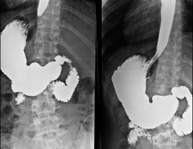

- EGDT (Oesophageal-gastro-duodenal transit)

Diagnostic test to obtain moving radiological images of the oesophagus, stomach and duodenum using X-rays (fluoroscopy) and an opaque barium contrast agent administered orally.